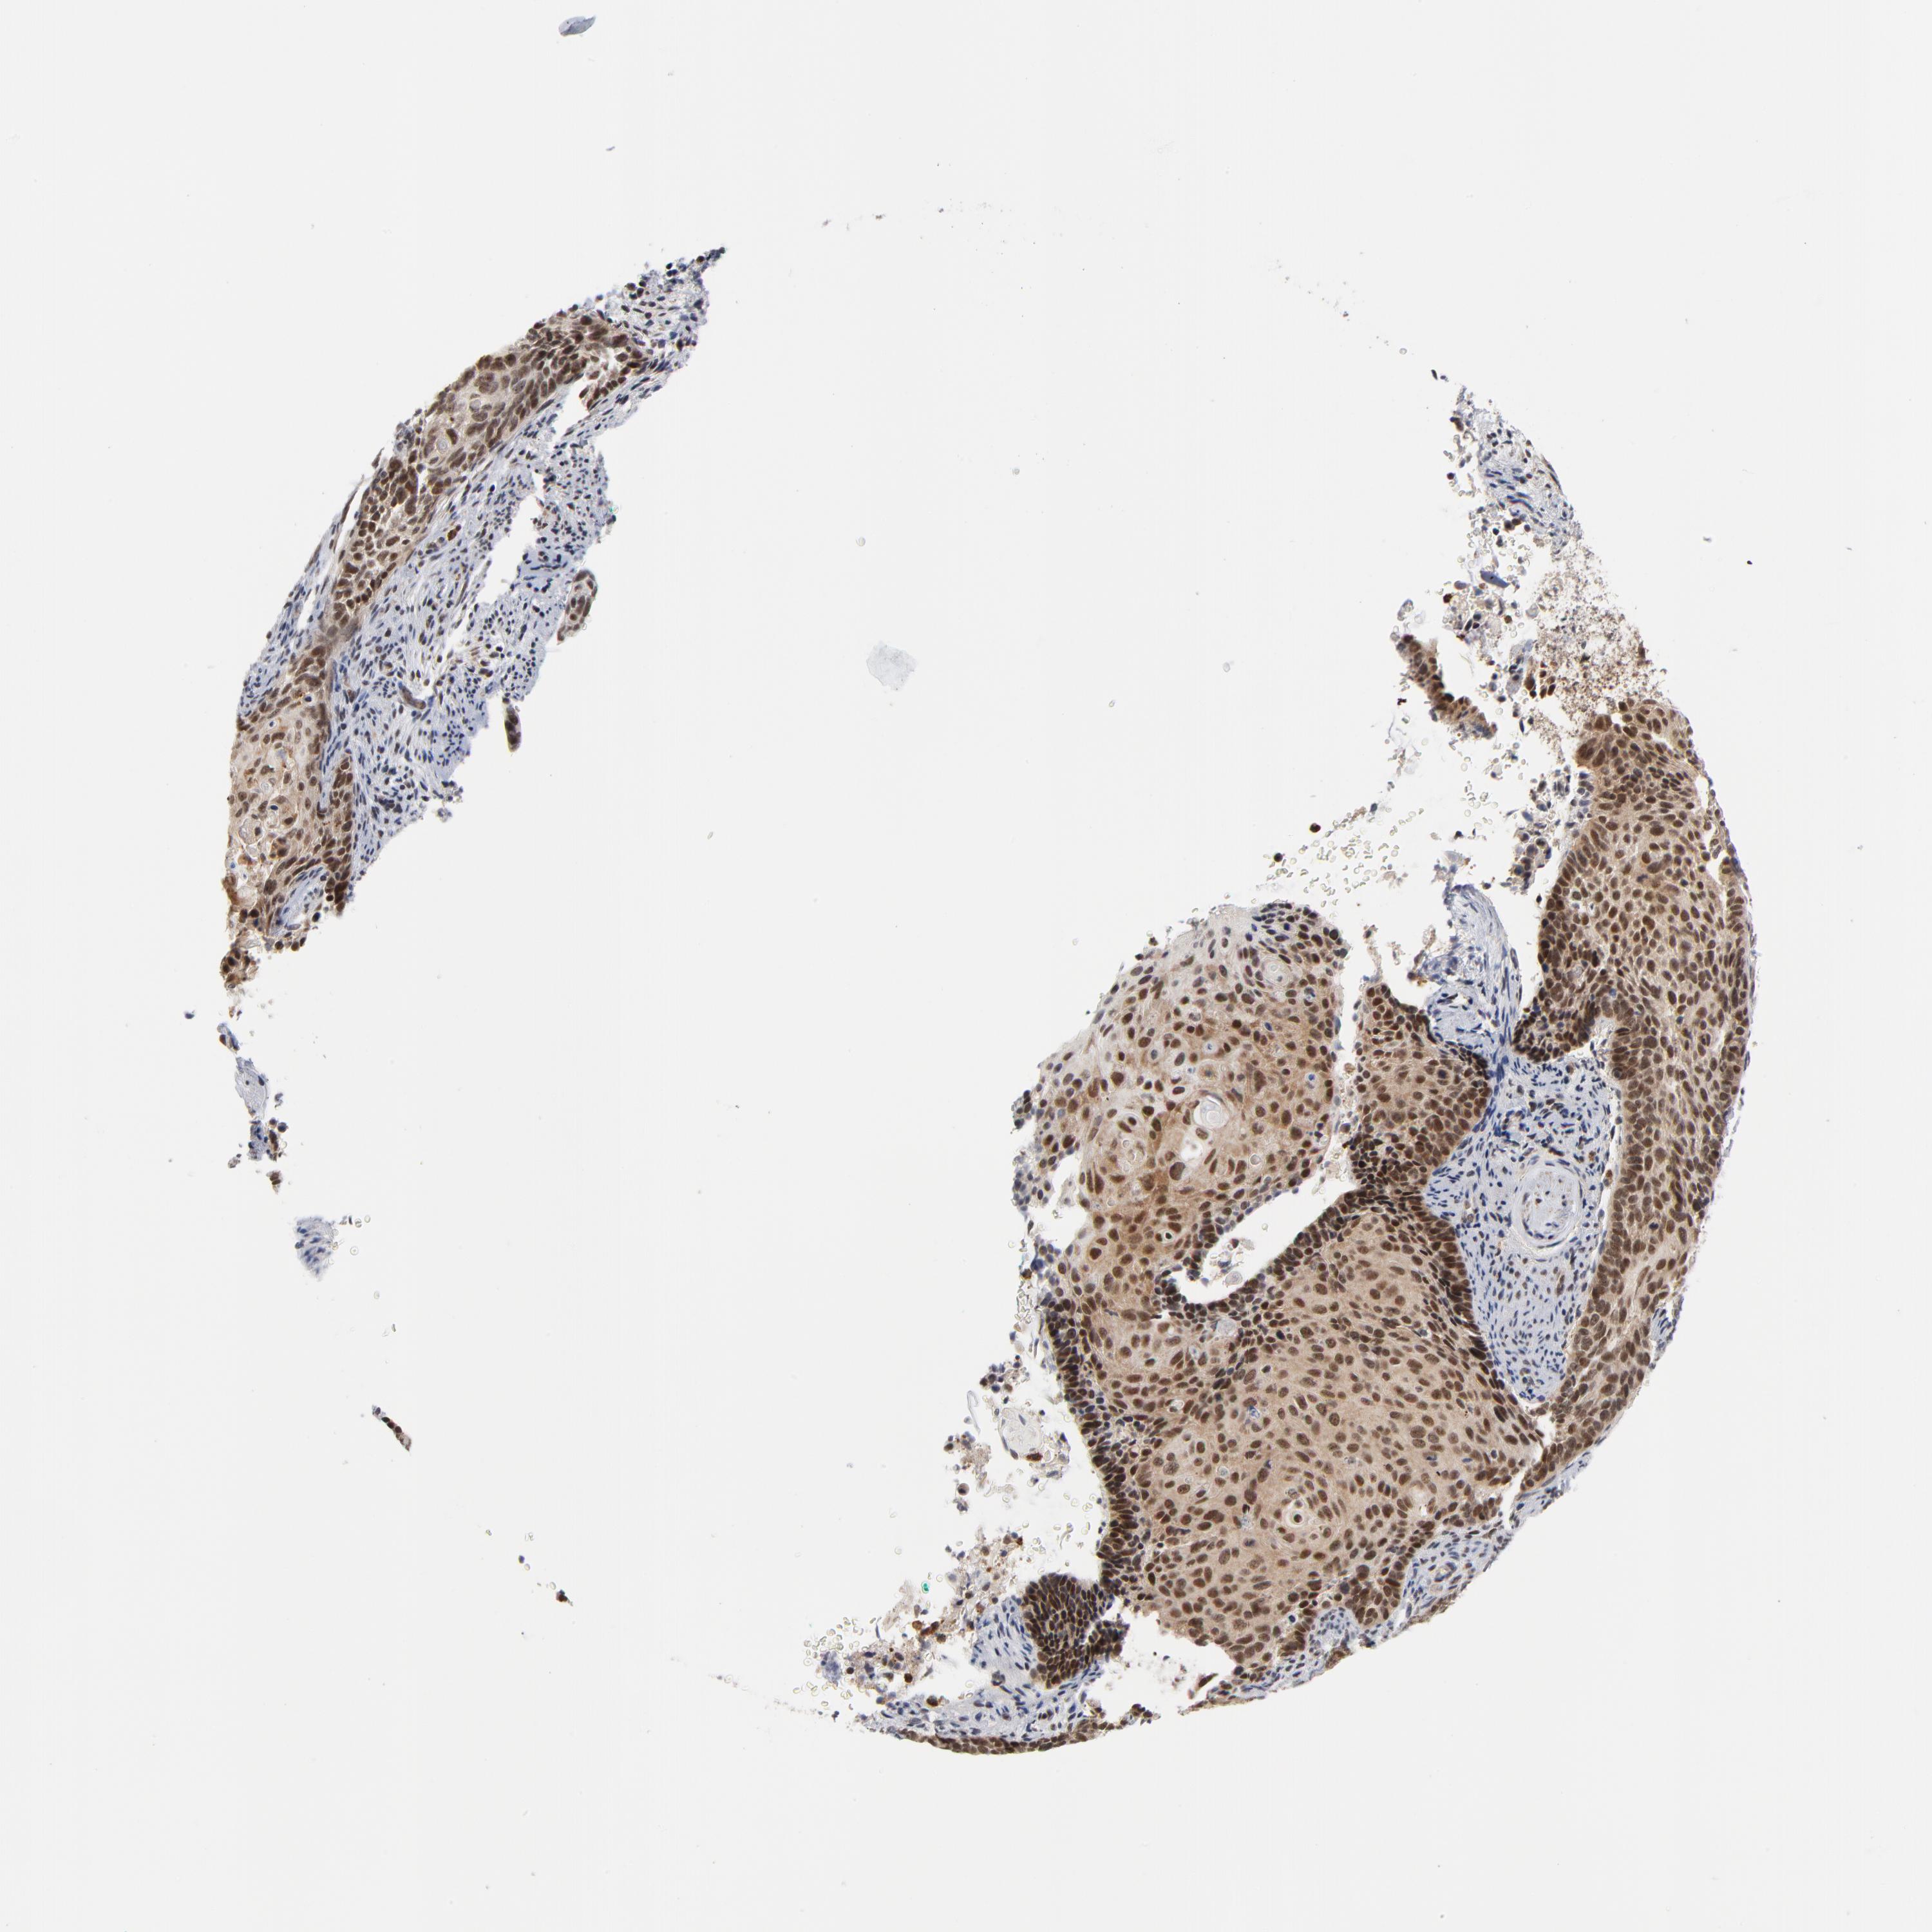

CERVICAL CANCER - Protein expressioni

A mouse-over function shows sample information and annotation data. Click on an image to view it in a full screen mode. Samples can be filtered based on level of antibody staining by selecting one or several of the following categories: high, medium, low and not detected. The assay and annotation is described here.

Note that samples used for immunohistochemistry by the Human Protein Atlas do not correspond to samples in the TCGA dataset.

Antibody stainingi

Antibody staining in the annotated cell types in the current human tissue is reported as not detected, low, medium, or high, based on conventional immunohistochemistry profiling in selected tissues. This score is based on the combination of the staining intensity and fraction of stained cells.

Each image is clickable and will lead to virtual microscopy that enables deeper exploration of all samples and also displays staining intensity scores, fraction scores and subcellular localization as well as patient and tissue information for each sample.

Antibody HPA003152

Antibody HPA003274

Staining

High

Medium

Low

Not detected

Intensity

Strong

Moderate

Weak

Negative

Quantity

>75%

75%-25%

<25%

None

Location

Nuclear

Cytoplasmic/membranous

Cytoplasmic/membranous,nuclear

Squamous cell carcinoma, NOS

Adenocarcinoma, NOS